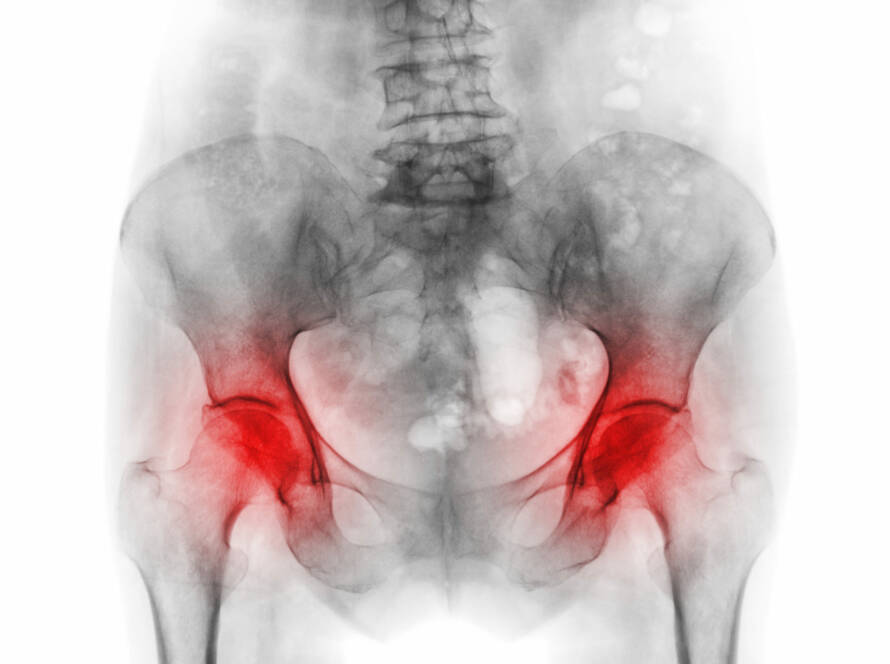

Il apparait de plus en plus, que de discrètes anomalies des structures autour de la hanche, résultant en un conflit fémoro-acétabulaire (FAI), peuvent être considérées dans certains cas, comme un facteur contribuant à l’arthrose du sujet jeune.

L’arthrose ou maladie dégénérative des articulations est le type d’arthrite le plus courant …

Le traitement conservateur, ou non-chirurgical est efficace aux stades précoces de l’arthrite. La prise en charge conservatrice inclut la perte de poids, le changement d’activité, les médicaments anti-inflammatoires ou les injections de cortisone.